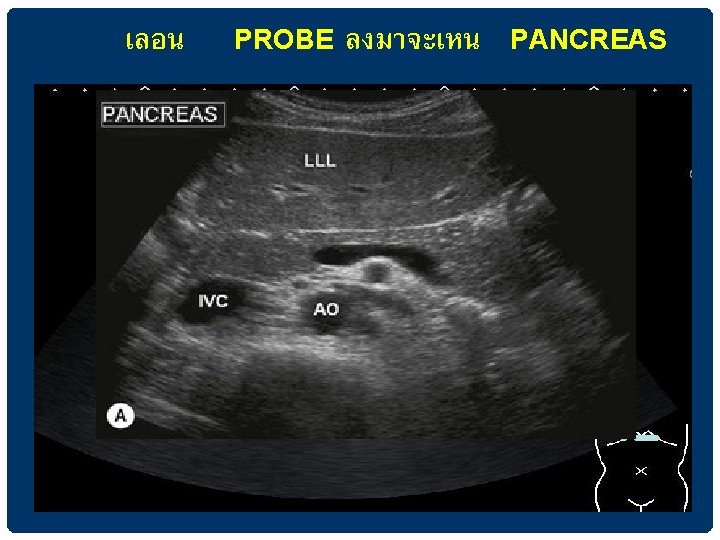

เหน PANCREAS ในการตรวจ SAGITTAL VIEW IN EPIGASTRIUM